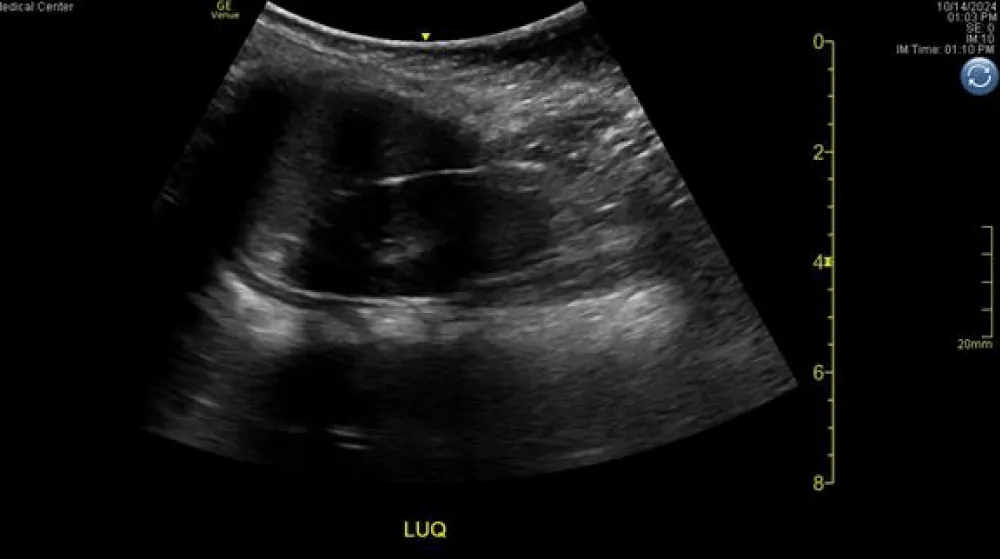

Because of questions surrounding the history of patient’s fall, the care team assessed the pre-test probability of IAI was sufficient to warrant imaging, so a point-of-care FAST exam was performed for diagnostic purposes using a Fujifilm Sonosite PX ultrasound system (Fujifilm Sonosite, Bothwell, WA) with a 1-5 MHz curvilinear probe on abdominal exam settings. The operator was an emergency medicine resident physician on an ultrasound rotation, supervised in the room by ultrasound fellowship faculty. The left upper quadrant window was significant for an anechoic stripe in the subdiaphragmatic area, concerning free fluid (Figure 1 and Video 1.) To assess whether the anechoic stripe was a blood vessel, color doppler was placed over it, with no indication of directional flow.

Video 1: Cine loop of the initial LUQ FAST view obtained on the Fujifilm Sonosite PX ultrasound system.